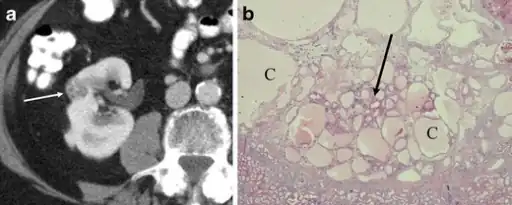

a,b)Renal oncocytoma with cystic change.

Renal oncocytoma of the right kidney at CT.